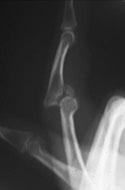

See the image below.

Acute dorsal proximal interphalangeal joint fracture-dislocation.